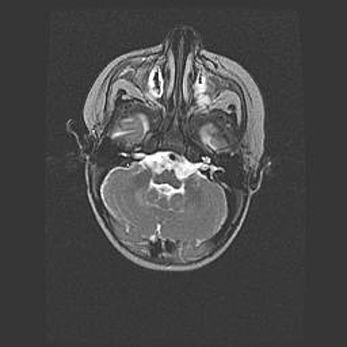

Мальформация Денди-Уокера. Киста задней черепной ямки.

Агенезия мозолистого тела.

Возраст: 2,5 месяца

Вес: 2420 г

Пол: женский

Окружность головы: 37 см

Срок гестации: 32 недели

Мальформация Денди—Уокера — редкий вид патологии ЦНС, представляющий собой врожденный порок развития каудального отдела ствола и червя мозжечка, ведущий к неполному раскрытию срединной (Мажанди) и латеральных (Лушка) апертур IV желудочка мозга. Для этогно синдрома характерна триада симптомов: гипотрофия червя мозжечка и/или полушарий мозжечка, кисты задней черепной ямки, гидроцефалия различной степени. В 70% случаев порок сочетается и с другими аномалиями головного мозга, в частности с агенезией мозолистого тела.